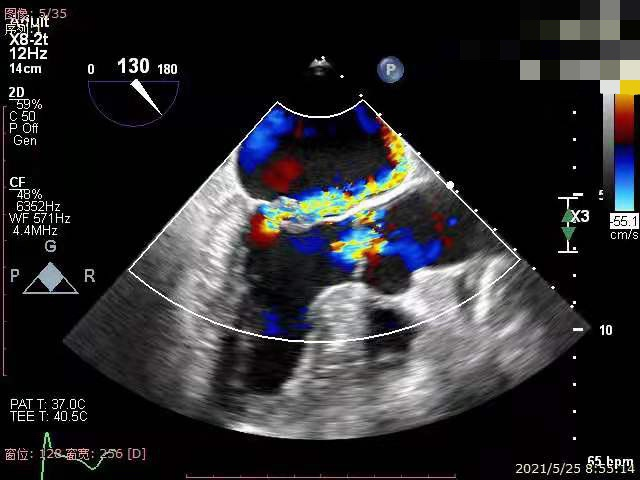

术前,罗建方、范瑞新教授团队进行了多次缜密术前讨论,最后决定为患者采用DragonFly™二尖瓣瓣膜夹。经充分的术前讨论后,心内科罗建方、范瑞新教授团队,在超声指导下,麻醉和体外循环团队保驾护航,瓣膜夹平稳释放,成功植入一枚DragonFly™瓣膜夹,随即进行DSA及心脏超声复查,观察到植入的瓣膜夹位置精确,患者二尖瓣反流从4+减少到1+以下,手术取得了圆满成功。